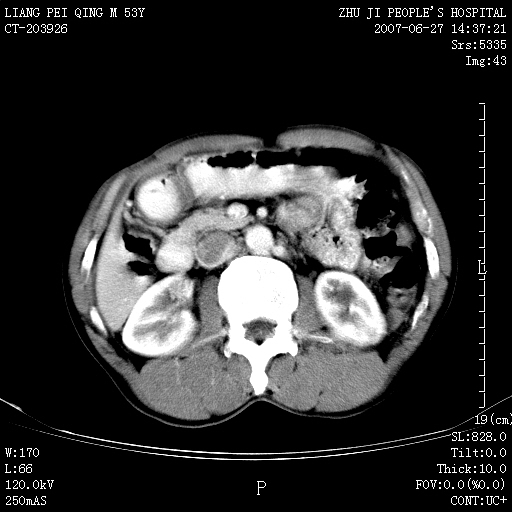

以下是引用余辉在2007-6-27 18:46:00的发言:[br]病灶多发,内可见大片状低密度区,病灶病灶等密度区轻度强化,动脉期后期病灶低密度区与高密度区对度增加,考虑1淋巴瘤2转移瘤3血管内皮细胞瘤(不知有否静脉期及延迟期扫描)

以下是引用zzzzhhhhaaaannnn在2007-6-27 20:44:00的发言:[br]脾脏 肋骨转移可能性大,下腔静脉内有癌栓

以下是引用狙击手在2007-6-28 10:35:00的发言:[br]1:定位:来源于脾脏。2:强化:强化,但不均匀。3:下腔静脉癌栓?下腔静脉充填不均匀与增强时间有关,延时即可明确。4:肋骨破坏?看起来并不确切。综上考虑几个最常见诊断:1;淋巴管瘤;2;血管内皮肉瘤(高度恶性,早期即可转移,常见肝,肺,骨)3;转移瘤(无特征性,只有肝或其它腹腔脏器有类似病变时,才可提示之)